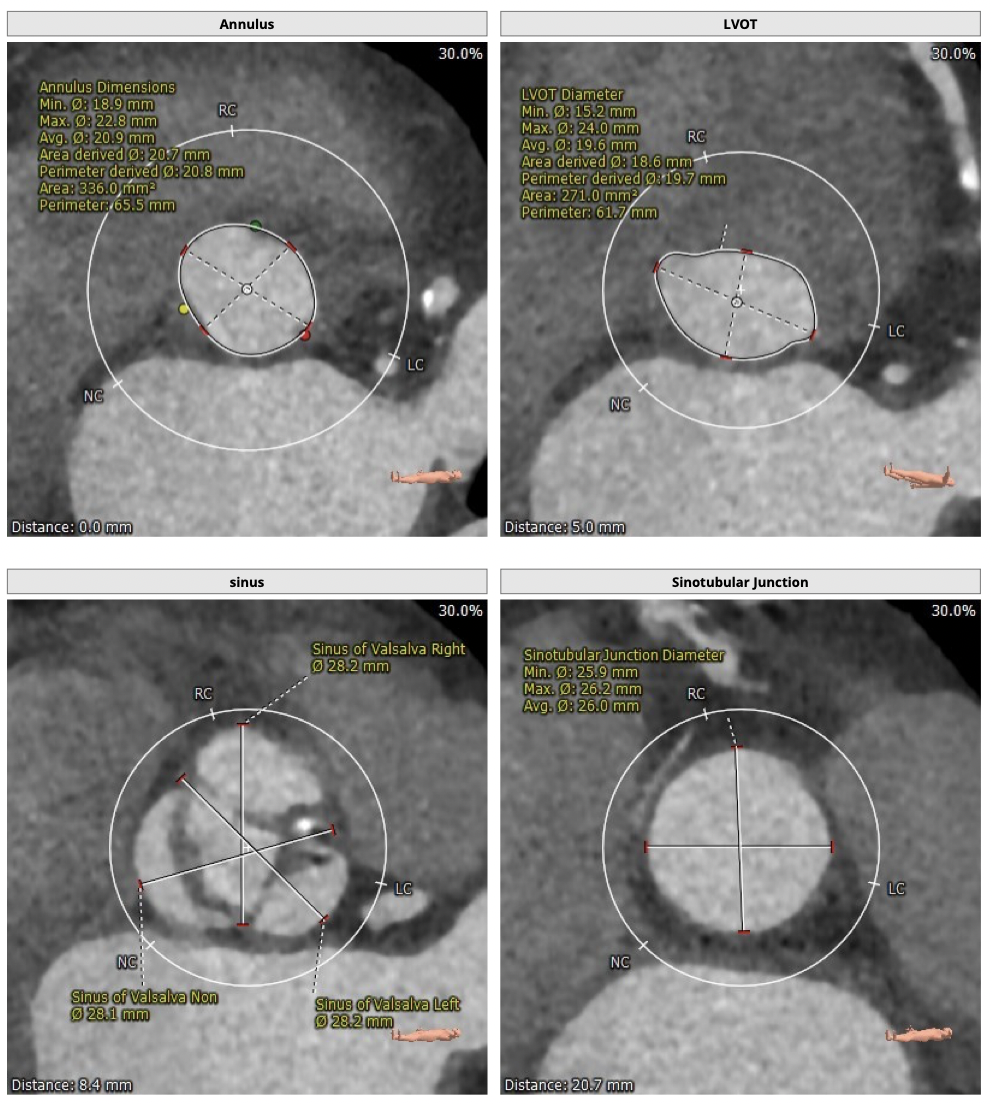

主动脉CT

难点分析:

*患者为TYPE1型二叶瓣,左右融合,重度钙化,融合脊难以推开,瓣膜释放后具有一定瓣周漏风险;

*心脏角度为57°,横位心,输送器过瓣难度增加,瓣膜植入同轴性差,瓣膜释放更易移位,增加了操作的难度;

制定策略:

经分析研判,拟从右侧股动脉穿刺入路,使用20mm球囊预扩,采取downsize手术策略,选用L23号的VenusA-Valve瓣膜,因患者为横位心,瓣膜释放同轴性差,容易发生移位,故采用VenusA-Plus可回收输送系统确保瓣膜的稳定释放,瓣膜释放后结合造影和超声情况,决定是否后扩。